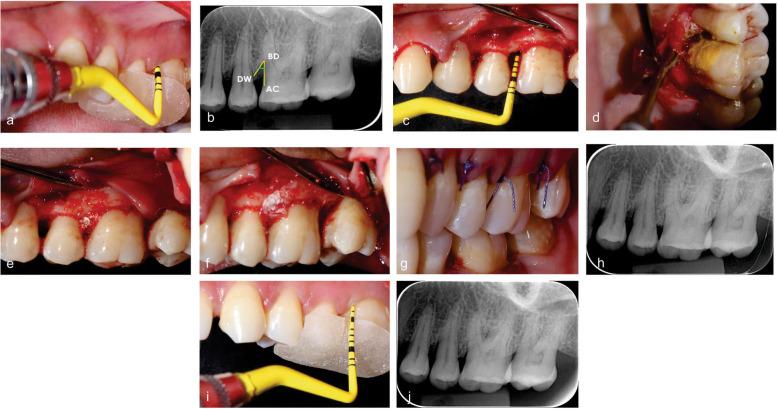

The concept of periodontal regeneration has been revolutionised since the introduction of growth factors and bioactive bone substitutes which ensures optimal regeneration of the diseased periodontium. The aim of the present study was to evaluate the efficacy of Amniotic membrane + Biphasic Calcium phosphate as compared to Collagen membrane + Biphasic Calcium phosphate for the management of periodontal intrabony defects.

METHODS

自生长因子和生物活性骨替代物引入以来,牙周再生的概念发生了革命性变化,这确保了患病牙周组织的最佳再生。本研究的目的是评估羊膜+双相磷酸钙与胶原膜+双相磷酸钙治疗牙周骨内缺损的疗效。

根据特定的纳入和排除标准,招募50例全身健康的局限性中度至重度牙周炎患者,这些部位在口腔根尖片(IOPAR)和骨探测中检测到探诊袋深度(PPD)≥6mm且骨内成分≥3mm。通过计算机生成的表格将他们随机分配到胶原膜+双相磷酸钙组和羊膜+双相磷酸钙组。在基线和6个月时测量骨填充量、探诊袋深度变化、临床附着水平。